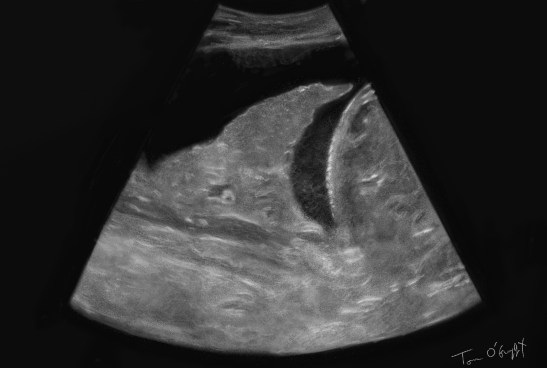

pleuresie echographie epanchement pleural

épanchement pleural en échographie

Pleurésie et épanchement pleural